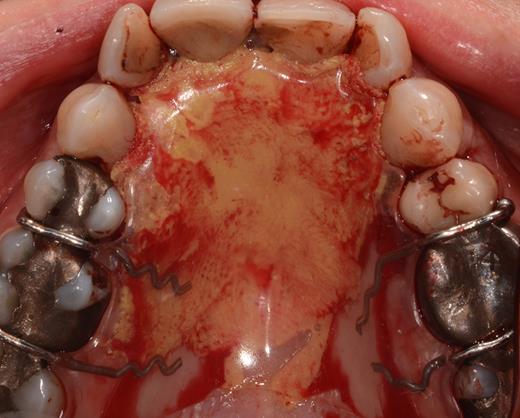

After a sulcular incision on the palatal side from teeth 15 to 25 and an incision in the midline of the palate omitting the incisive papilla and the two orifices of the NPD, two full-thickness mucoperiosteal flaps were raised. Thereafter, the incisive papilla and the whole contents of the incisive canal were enucleated (Figs 4–6). The bony incisive canal was filled with autologous bone harvested from the palatal region (bone scraper) (Fig. 7). A tension-free primary wound closure was achieved by moving the palatal flaps to the midline using single button and interdental vertical mattress sutures (Monocryl 4-0, Ethicon, Johnson & Johnson, USA) (Fig. 8). To avoid wound dehiscence and hematoma, an iodoforme gauze and a palatal plate were applied (Fig. 9). The patient was instructed to rinse three times a day with 0.1% chlorhexidine (formula hospitalis) for 2 weeks postoperatively. Sutures were removed after 14 days.

Preparation of the soft tissue of the incisive canal and the incisive papilla.